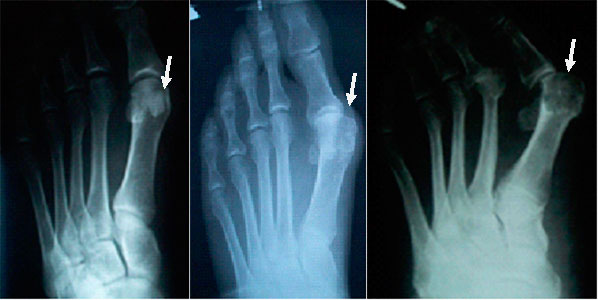

Диагностика вальгусной деформации и методы терапии

Диагноз вальгусной деформации стопы устанавливается на основе различных инструментальных исследований:

- рентгенография;